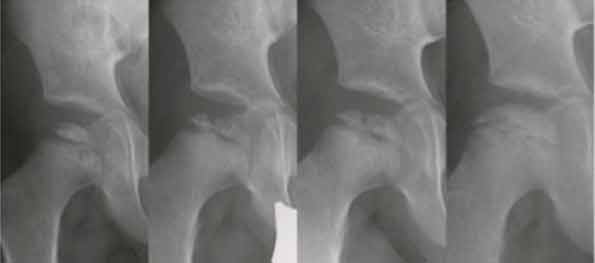

Der M. Perthes ist eine in Stadien verlaufende Erkrankung (Abb.1) des Hüftgelenkes (Altersgipfel 5 bis 10 Jahre) bei einem sonst gesunden Kind. Hierbei kommt es zu einer Nekrose (Absterben) des Hüftkopfes mit gleichzeitig einsetzenden Reparaturvorgängen. Jungen sind mit einem Verhältnis von 4:1 häufiger betroffen. Die Ursache des M. Perthes ist nicht vollständig geklärt. Diskutiert werden eine Minderdurchblutung des Hüftkopfes, Veränderungen der Zähflüssigkeit des Blutes, genetische sowie ernährungsbedingte Ursachen. Der natürliche Verlauf dieser Erkrankung wird durch folgende Faktoren beeinflusst: Alter, Bewegungsumfang und Geschlecht. Ziel der Therapie ist es, diejenigen Patienten herauszufiltern, die einen ungünstigen Verlauf nehmen und diese rechtzeitig, gegebenenfalls operativ zu behandeln. Grundlegendes Behandlungsziel ist der Erhalt der Beweglichkeit.

Prognose: Je älter der Patient bei Beginn der Erkrankung, desto schlechter die Prognose. Beginnt die Krankheit vor 6 Jahren, ist die Prognose unabhängig anderer Faktoren eher gut, während bei älteren Kindern bei Diagnosestellung eher schlechte Endresultate zu erwarten sind. Einen ebenfalls recht hohen Stellenwert bezüglich einer prognostischen Aussage haben der laterale Kernschatten und die Subluxation (Abb.2)

Abb. 1: Röntgenaufnahmen eines 3-jährigen Jungen mit M. Perthes der rechten Hüfte. Im Verlauf erkennbar sind die 4 Stadien der Erkrankung (v.l.n.r.): Kondensations-, Fragmentations- (6 Monate später), Reparations- (1 Jahr später) und Endstadium (3 Jahre später). Komplette restitutio ad integrum.

Abb. 2: Röntgenaufnahmen der rechten Hüfte eines 10-jährigen Jungen mit M. Perthes. (A) Ausgeprägte laterale Kalzifikationen am Hüftkopf (prognostisch ungünstig). (B) Endstadium der Erkrankung 5 Jahre später mit einer Coxa magna et plana.